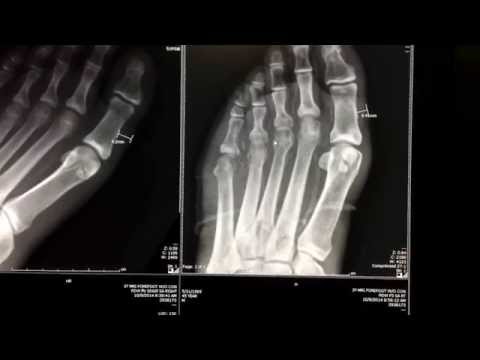

Radiology and diabetes mellitus. plain abdominal x-ray was highly sensitive (97. 4%), while abdominal computerized tomography was the most sensitive and specific diagnostic tool. a complicated. Diabetesmellitus, disorder of carbohydrate metabolism characterized by impaired ability of the body to produce or respond to insulin and thereby maintain proper levels of sugar in the blood. diabetes is a major cause of morbidity and mortality, though these outcomes are not due to the immediate effects of the disorder. they are instead related. 1. east diabetes mellitus x ray afr med j. 1991 dec;68(12):989-92. diabetes mellitus. ii: routine chest radiography. hamed ad(1), akinsola a. author information: (1)department of radiology, faculty of health sciences, obafemi awolowo university, ile-ife, nigeria. chest radiographs of 43 consecutive diabetic patients were evaluated with a view to determine their role as a routine investigation of patients with.

In a number diabetes mellitus x ray of published comparative studies, chest x-ray images from patients having ptb with diabetes mellitus (dm) have been described as ‘atypical’, mainly because they frequently involve the lower lung fields, often with cavities. [ 1, 2 ] a higher frequency of multi-lobar involvement has also been described among ptb with dm patients. [ 1 ]. In modern western societies by far the most common cause of charcot joints is diabetes mellitus, and therefore, the demographics of patients matches those of older diabetics. prevalence differs depending on the severity of diabetes mellitus 10: ~0. 1% in general diabetic population ~15% in high-risk diabetic population.

Additionally, diabetes mellitus is a negative diabetes mellitus x ray prognostic factor for post-fracture mortality among patients with hip fractures [17,113,114]. however, despite the increased fracture risk, patients with t2dm show a higher bmd at the femoral neck and lumbar spine in conventional dual-energy x-ray absorptiometry (dexa) scans. Symptoms. diabetes symptoms vary depending on how much your blood sugar is elevated. some people, especially those with prediabetes or type 2 diabetes, may not experience symptoms initially. in type 1 diabetes, symptoms tend to come on quickly and be more severe. some of the signs and symptoms of type 1 and type 2 diabetes are: increased thirst.